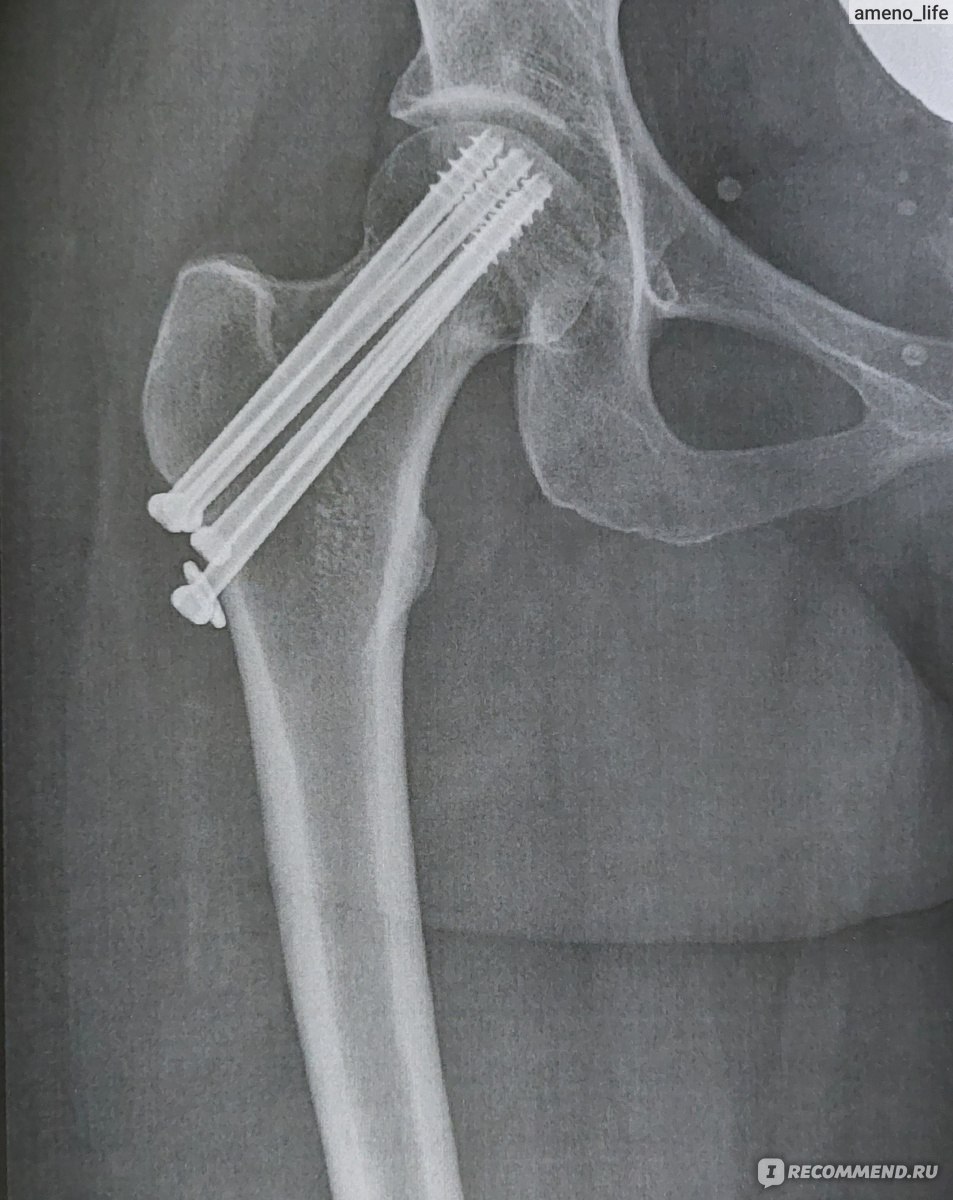

Иллюстрации и снимки, связанные с остеопенией шейки бедра